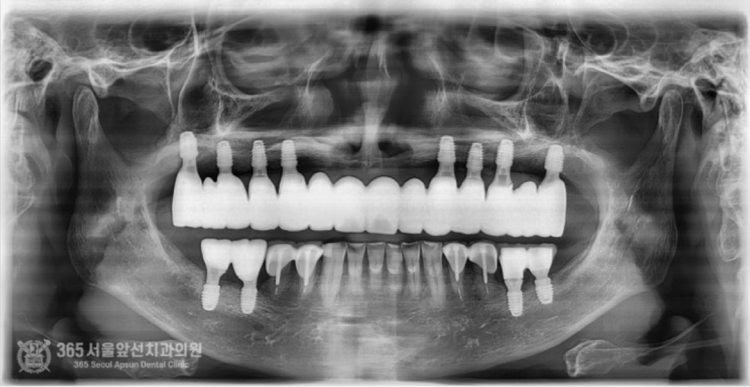

촬영일시: 2024.06.07. 처음 오셨을때 엑스레이 사진입니다. 윗턱과 아래턱 모두 뼈가 매우 적은편입니다. 특히 윗턱의 앞니쪽은 뼈가 고작 3mm밖에 존재하지 않았습니다. 매우 난증례에 해당한다고 볼 수 있겠습니다. 앞니 부위 뼈가 매우 부족하고(3mm) 어금니쪽도 전체적으로 뼈가 매우 적었습니다. 앞니와 어금니의 부족한 뼈를 만들어내면서 임플란트 식립을 계획했습니다. 통상적으로 윗턱에서 뼈가 부족할때 사용하는 수술방법으로 상악동거상술이라는 잘 알려진 술식이있는데요. 상기 환자분의 경우, 앞니쪽까지도 뼈가 부족했기에 코로 접근해서 부족한 뼈를 만들어 내는 비강거상술까지 동반하여 임플란트 수술을 진행했습니다. 촬영일시: 2024.08.10. 좌우측 상악동 거상과 비강거상을 동반하여 윗턱에 임플란트 8개를 식립했습니다. 지금까지 만나뵈었던 많은 환자분들 중 뼈의 상태가 매우 안좋은 편에 속하셨으며 매우 난해한 증례였습니다. 그렇지만 수술은 성공적으로 잘 마무리되었습니다. 위아래 전체 임플란트를 식립한 후 엑스레이 사진입니다. 임플란트가 가지런히 잘 배열되어있습니다 ㅎㅎ 지르코니아라는 재료를 사용하여 치아색상으로 단단하게 보철물도 제작했습니다. 촬영일시: 2024.12.29. 최종적으로 마무리된 엑스레이 사진입니다. 촬영일시: 2024.12.29. -노란색: 원래 환자분의 윗턱뼈 -주황색: 상악동거상술을 통해 만들어진 뼈 -보라색: 비강거상술을 통해 만들어진 뼈 최종적으로 치료가 완료된 후 구강내 사진입니다.